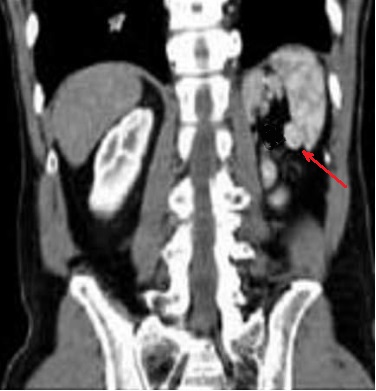

Image

echographique une rate poly-splénique siue au hile

de la rate avec aspect des nodules fragmentees

hilaire hypoechogene . En differentié avec

image arrondie aechogène des vaisseaux hilaires

de la rate . |